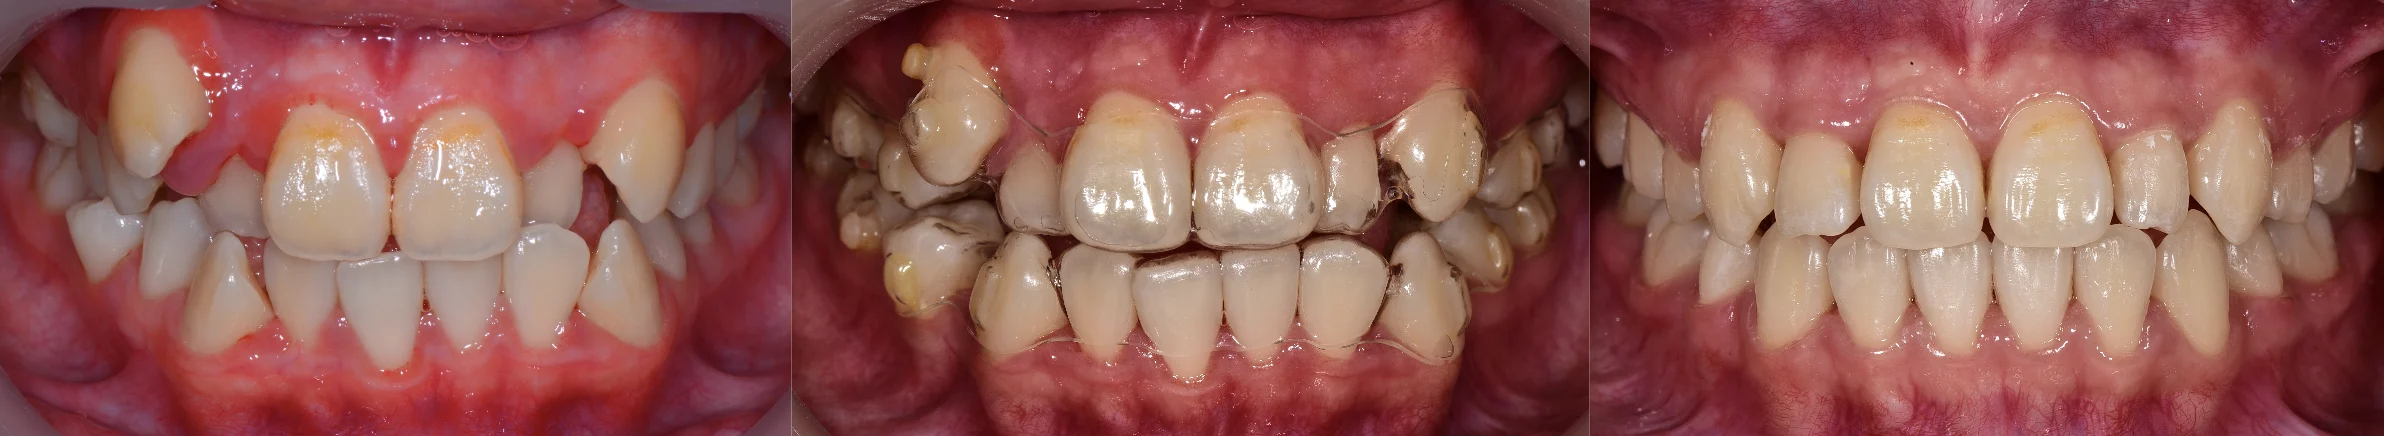

拔牙矯正案例-虎牙